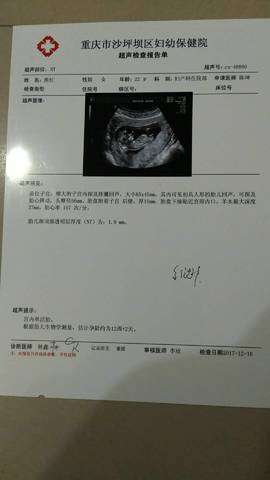

怀孕5个月,也就是17周,胎儿长约1825厘米,重约250300克,差不多有一个苹果那么大。怀孕第17周,胎心发育基本完成,心跳强烈,约145次/分钟。准妈妈可以借助听诊器听到胎儿强有力的心跳。胎儿强有力的心跳可以减少准妈妈生孩子的恐惧,增加她们的信心。胎儿的循环系统和尿道完全处于正常工作状态,肺部也开始工作。

双顶径平均4.25±0.53cm,腹围平均12.41 l.89cm,股骨长2.71±0.46cm 3、孕19周:胎儿从头至臀约15cm,重225克。双顶径平均4.52±0.53cm,腹围平均13.59±2.30cm,股骨长3.03±0.5cm . 4、孕2 0周:胎儿头至臀长约16.5cm,头至趾长25.4cm,重250克。